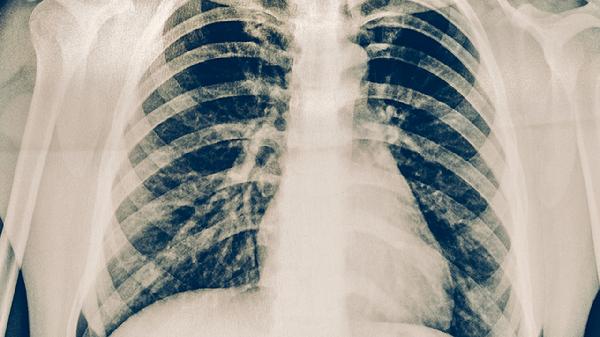

继发性肺结核患者服用抗结核药物后出现尿酸升高,可通过调整饮食结构、增加水分摄入、适度运动、药物干预及定期监测尿酸等方式改善。尿酸升高可能与吡嗪酰胺等药物抑制尿酸排泄有关,通常伴随关节疼痛、痛风等症状。